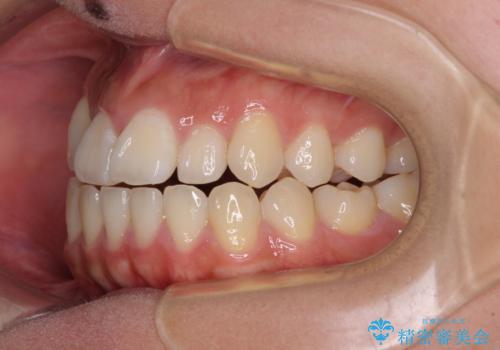

- 前歯の開咬と、上顎前歯の八重歯やデコボコを気にして来院された患者様です。

上顎歯列が狭窄していたため、急速拡大装置により上顎骨を側方に拡大し、その後ワイヤー装置にて矯正治療を行うこととしました。

上顎骨を拡大することで、八重歯やデコボコを歯列に収めることができ、下顎の歯が外に位置していた奥歯の咬み合わせも改善することができました。